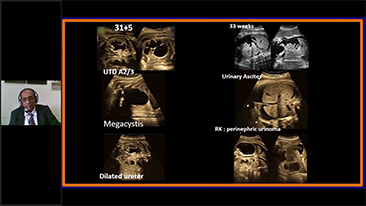

??? ??? ??? ???? ? ?? ???? ??? ? ?????

?? ?? ?? ??? ?? ?? ?? ???? ?? ???? OBG ?????? ?????. ?? ??, ?????(CNS) ??? ?? ?? ??? ?? ? ?????. ???? ?? ??? ?? ??? ??? ??? ?? MSP? 2D ????? ?? ???? ?????. ??? ?? ?? ? ??? ??? ???? ?? ???? ? ????.